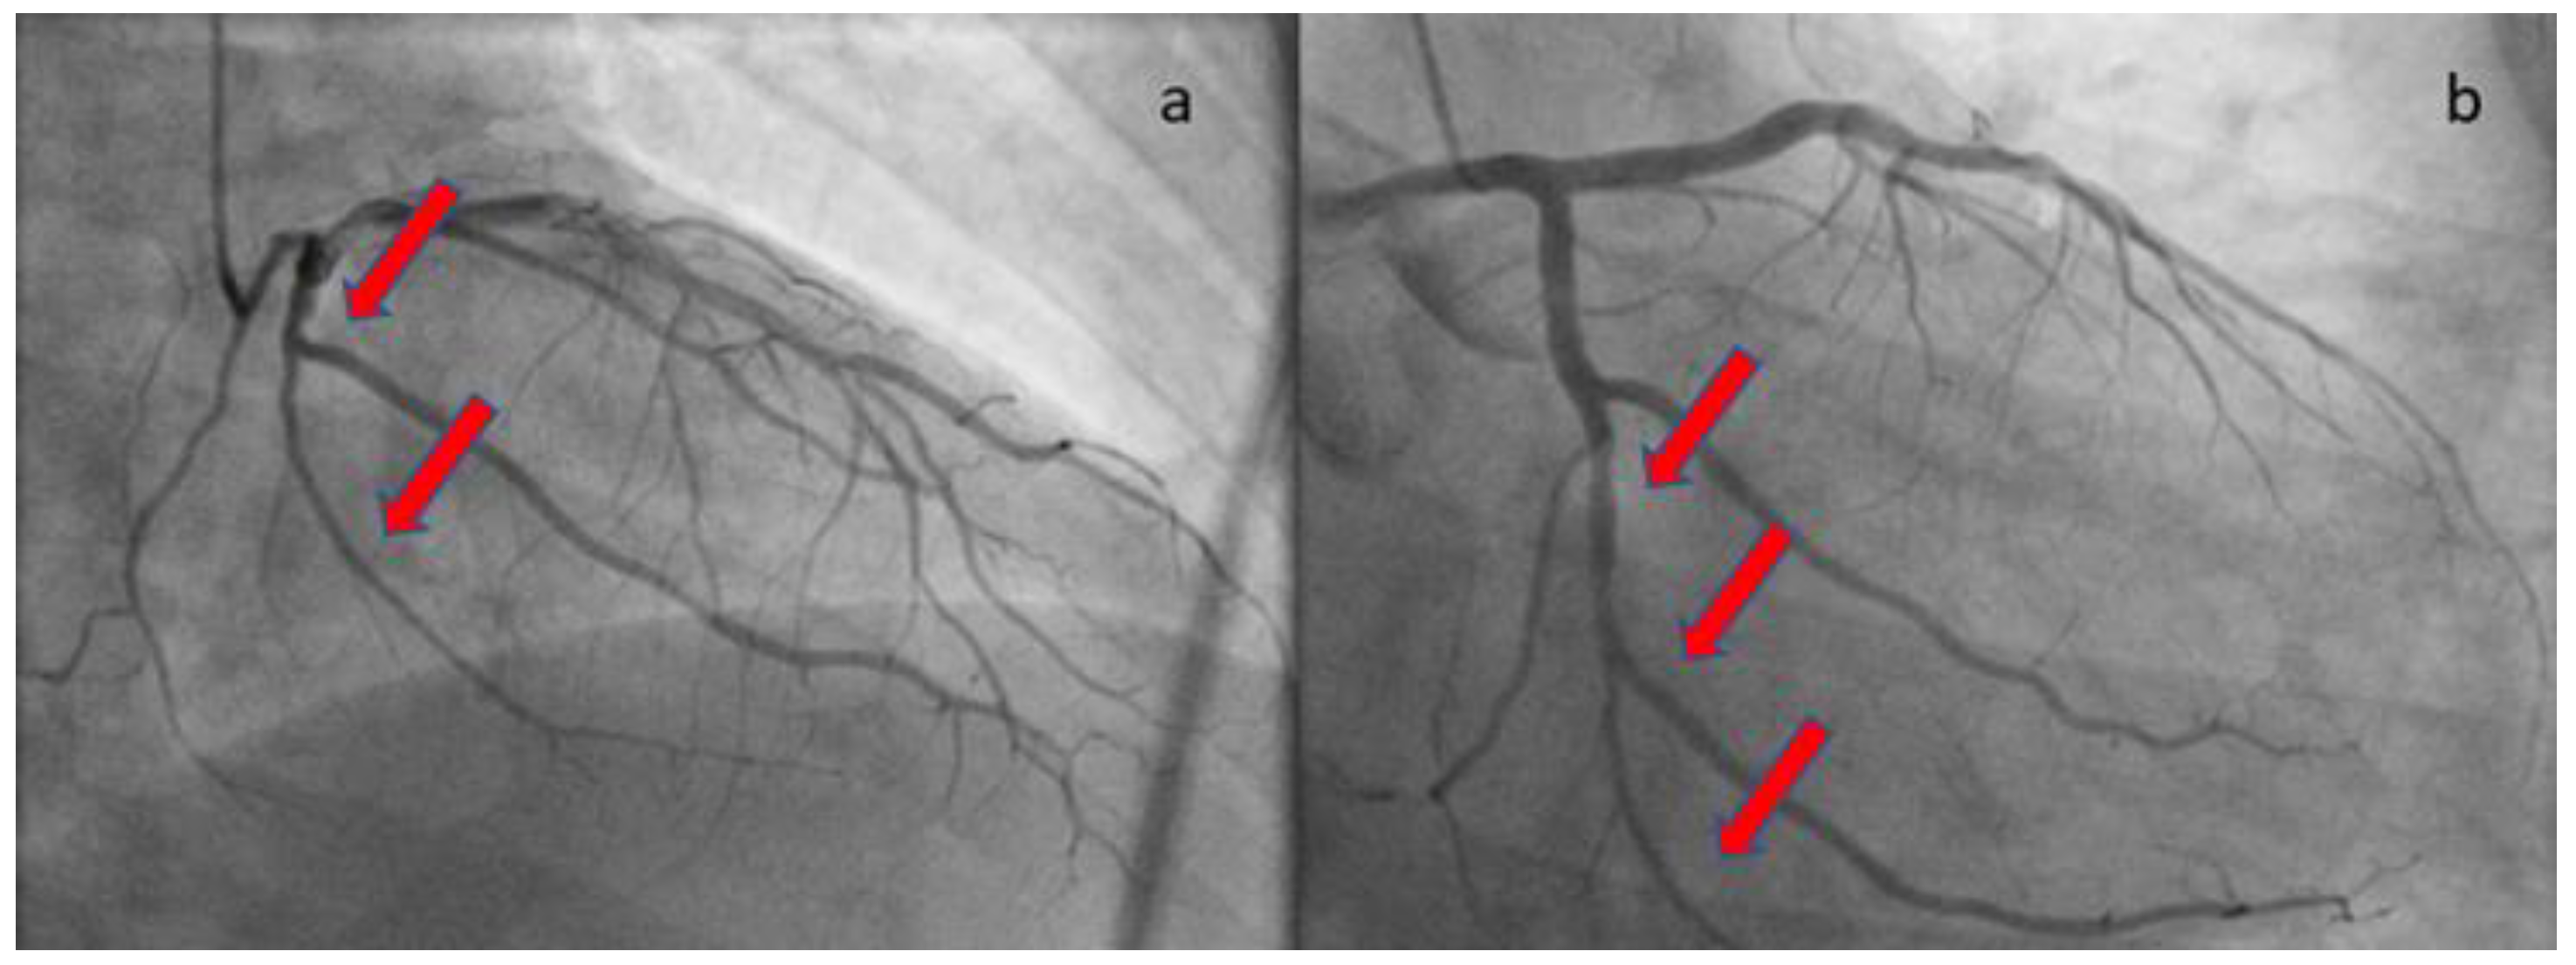

The patient was loaded with aspirin (ASA) 325mg and ticagrelor 180mg and was transferred to the catheterization laboratory, where emergent coronary angiography was performed via right radial access. During contrast injection in the left coronary system, a long smooth 70-80% stenosis was revealed along the mid portion of left circumflex artery (LCX) extending to the distal part of the vessel, including an obtuse marginal branch (Figure 2). Despite intracoronary administration of nitroglycerin, the narrowing along the vessels remained unchanged, hence we proceeded with intracoronary imaging using optical coherent tomography that revealed SCAD (Figure 3). The remainder of the coronary tree was normal.

Figure 2. Coronary angiography revealing a long smooth lesion in LCX. The red arrows show the long lesion. (a) RAO cranial angiographic view; (b) RAO caudal angiographic view.